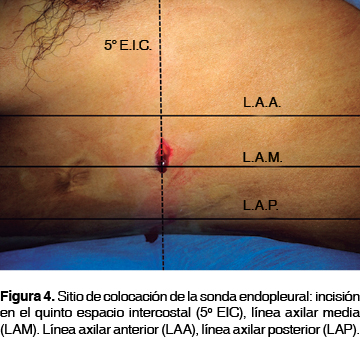

En todos los pacientes se emplearon sondas Argyle™ Thoracic Catheter Straight 32 Fr (10.7 mm) x 20" (51 cm) (figura 2), las cuales fueron colocadas entre las líneas axilar anterior y media en el quinto espacio intercostal (figuras 3 y 4), fijadas con seda 1 a la piel (figura 5) y conectadas a un sistema de drenaje torácico de tres cámaras Atrium™ Ocean Water Seal Chest 2002 Single Collection (figura 6) con succión continua a 20 cmH2O. Durante el procedimiento se les administró tramadol 100 mg por vía intravenosa e infiltró en el sitio de colocación con lidocaína al 2% con epinefrina a una dosis de 7 mg/kg, después se les proporcionó antibioticoterapia con ceftriaxona 1 g cada 12 horas por vía intravenosa durante el período de permanencia de la sonda y analgesia con ibuprofeno 400 mg cada ocho horas por vía enteral si estaba disponible la misma, hasta el retiro de la sonda; además, recibieron curación diaria del sitio de inserción de la sonda -consistente en lavado del sitio quirúrgico con iodopovidona y movilización gentil de la sonda, verificando su permeabilidad- bajo analgesia con tramadol y con posterior control radiográfico.